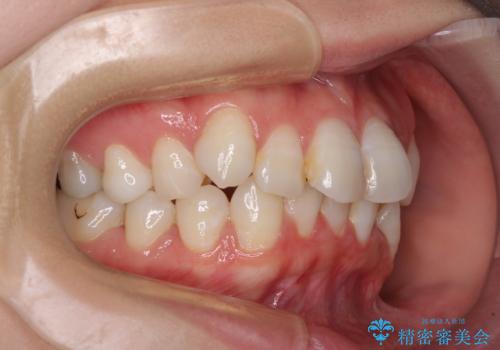

- 上下前歯のデコボコを改善したいとのことで来院された患者様です。

マウスピースを長時間装着し続ける自信はあまりないとのことでしたが、目立たない装置であれば頑張って装着するとのことで、インビザラインによる矯正治療を行うこととしました。

初めの1年くらいは何とか頑張って装着してくださいましたが、途中から変化をあまり感じられなくなり、日々の装着時間は徐々に短くなってしまいました。

前歯のデコボコはもっと改善できましたが、3年半が経過し、初診時と比べたら大幅に良くなったとのことで終了することとなりました。